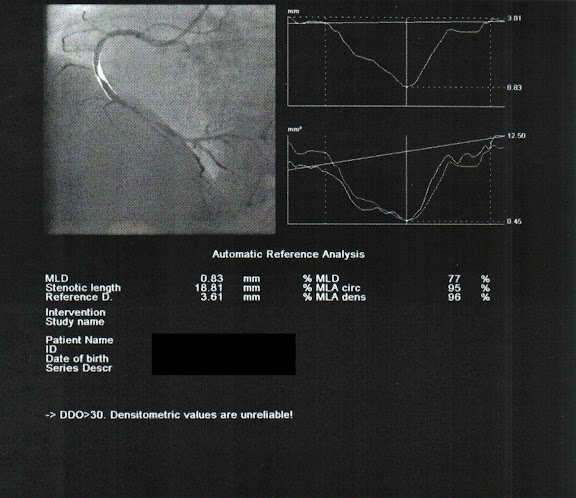

但不樂觀的是另一條血管上堵了兩個地方,整條血管長得像三節的蓮藕一樣。

經過電腦的計算,靠上方的第一個堵塞點塞住了95%。

第二個堵塞點塞住了98%,意思是可以看做是全塞住了,醫生說導線一穿過去時整個都堵死了差一點沒辦法穿過去。

處理方式先用3.0mm的氣球先撐開。

換另一個靠上方的位置一樣用3.0mm的氣球撐開一些。

因為血管比較粗,所以再換管徑大一點的3.5mm繼續撐大一點!

靠上方的位置同樣的也換成3.5mm用力撐大一點!!

撐開之後血流就正常多了。

等個5min後再觀察看看堵塞處有沒有縮回來,如果縮回來的話就一定要放支架了。

最後處理結果,用氣球擴張術處理完靠上方的堵塞點擴張後的堵塞是36%

靠下方的擴張完還有21%的堵塞率。